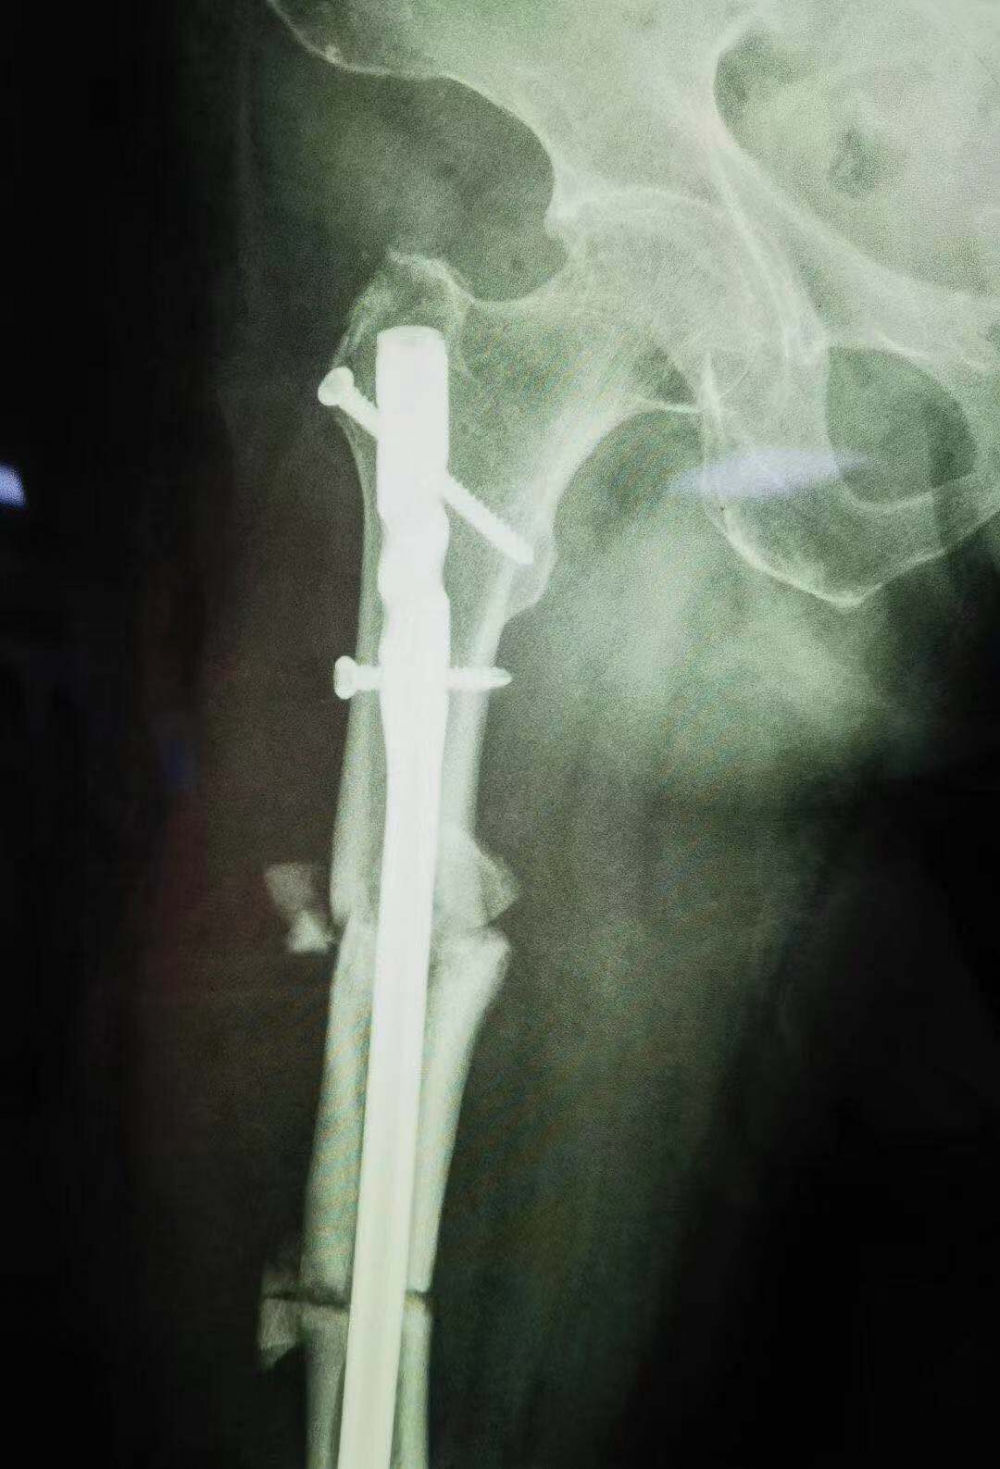

(股骨中段斷裂,上端有明顯畸形)

當她的X光片出來時,收治的醫(yī)生都被她的傷情嚇了一跳。原來此次她骨折的上端還有一處骨傷畸形愈合。這是什么情況呢?

原來張守蓮在三年前還摔傷過一次,當時在一家醫(yī)院進行了手法復位,但因操作不當,沒能復位成功,留下了后遺癥。三年來她都是以拄拐行走。